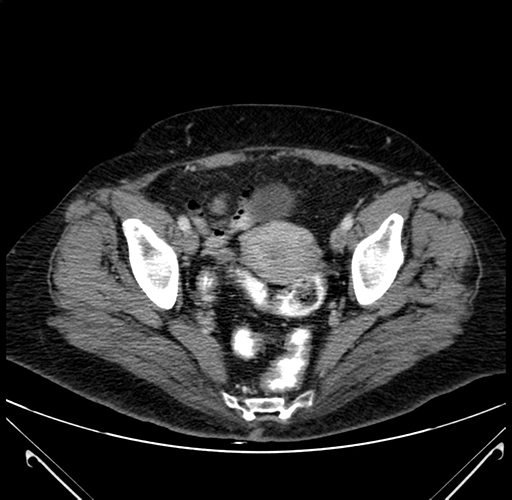

Axial Venous

Based on your CT findings, which issue(s) would give reason for "planned slowing down moment(s)" in this case?

Considering a standard right hepatectomy procedure, what step(s) of the operation would you do differently in this case?